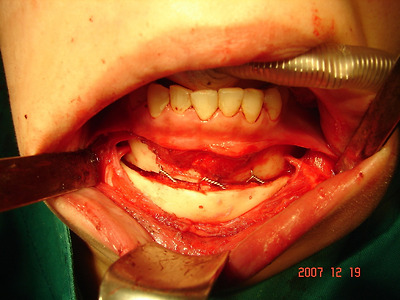

..사진설명: 턱끝 절골 수술후 턱끝 전진후 고정한 상태 -정상적인 수술내용.

무턱 수술에서 보존해야 할 턱뼈에서 올라오는 양쪽 아랫입술 신경을 잘 보존한 상태, 턱끝뼈를 잘라 앞으로 전진시킨 무턱 교정 수술 .